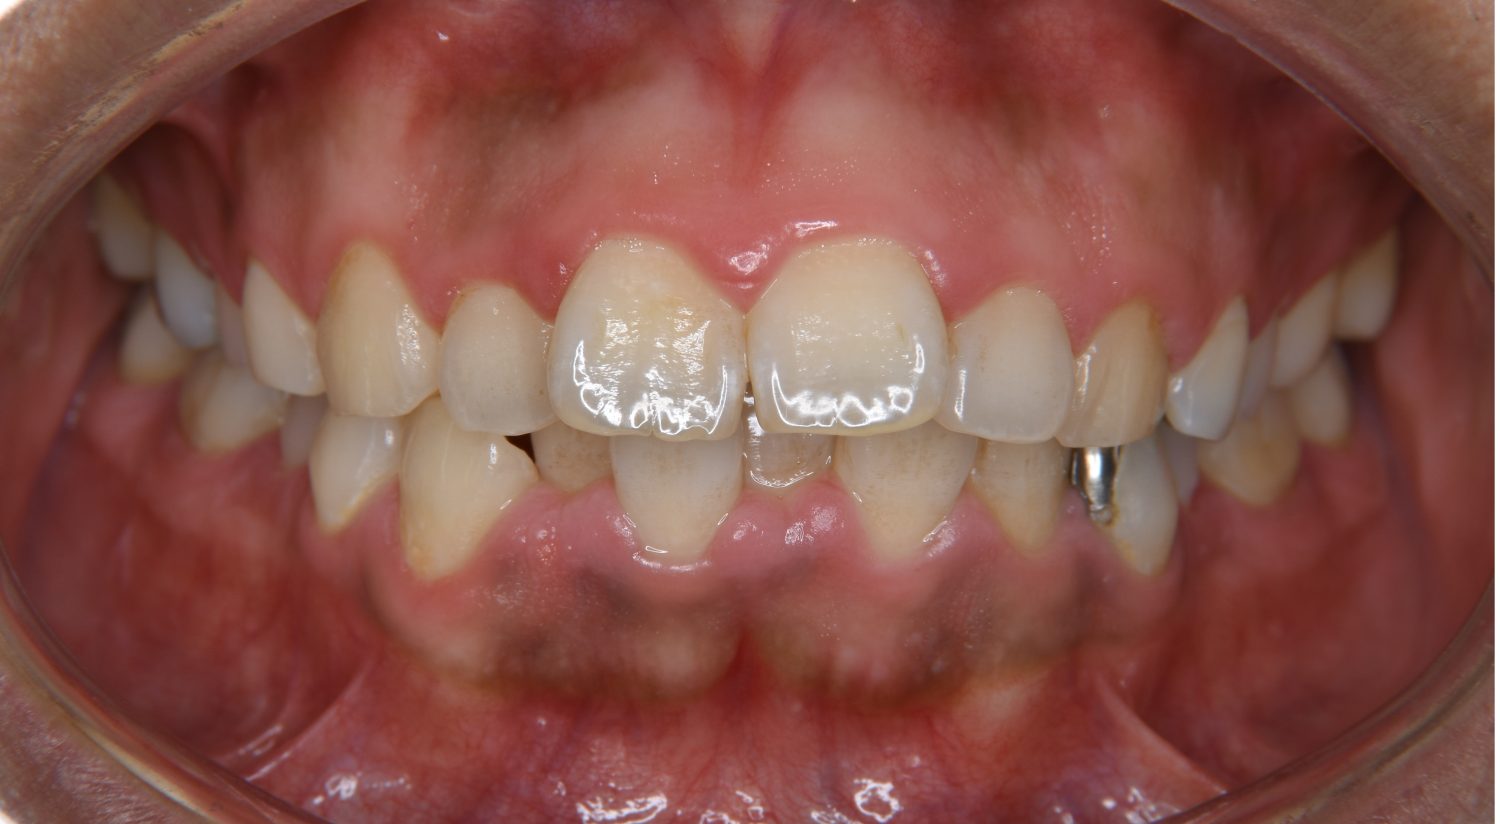

上顎前突の症例紹介①

Before

主訴

上の歯が出ている。歯並び全体が気になる。

治療内容

上顎両側第一小臼歯を抜歯し、上下ラビアルブラケット(唇側装置)に矯正用アンカースクリューを併用し治療を行いました。

治療費

1,000,000 円(税込)

治療期間

26ヶ月

通院回数

25回

想定されたリスク

※なし

上顎前歯の前突により口元の突出が認められました。上の左右の第一小臼歯を抜歯し上顎前歯を後退させることで口元の突出感は改善し、咬合も良好な状態となりました。